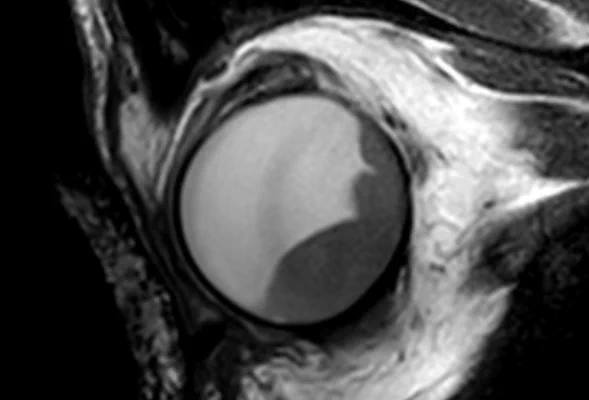

• 3DT1 SPIR Gd

3DT1 SPIR Gd

The isotropic resolution allows for accurate 3D assessment of the lesion dimensions.